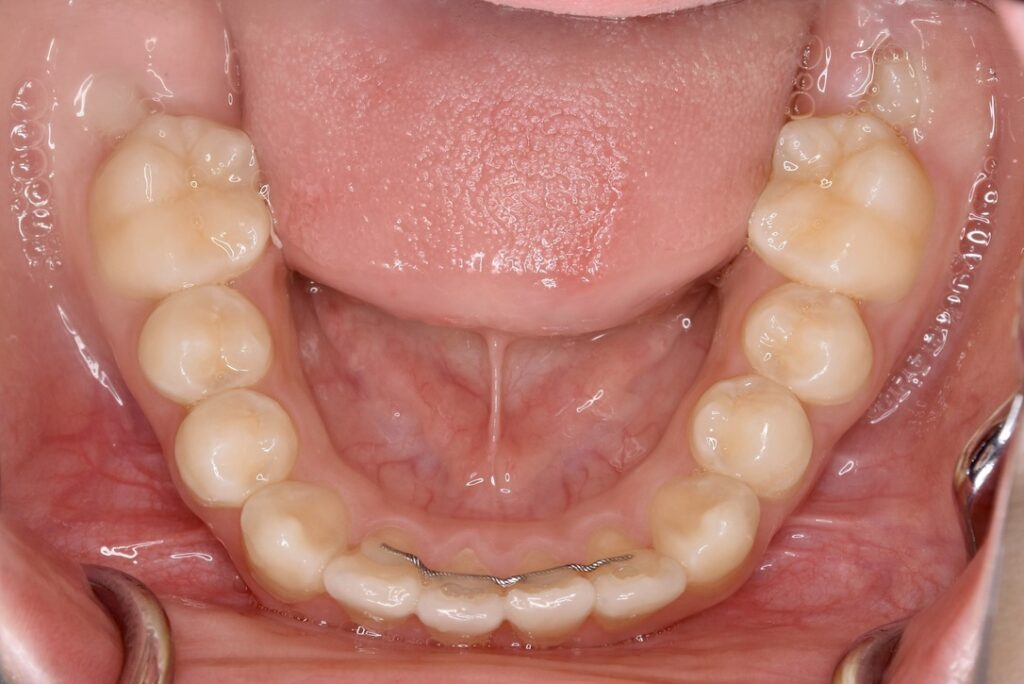

AFTER

診断名・主な症状 下顎前歯の叢生を伴う過蓋咬合

治療内容 上下の歯並びの幅を拡げつつ、前歯の関係を改善しました。

使用装置 急速拡大装置

リンガルアーチ

機能的矯正装置(マイオブレース)